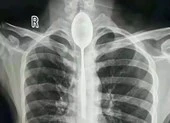

Phim chụp X-quang cho thấy chiếc chìa khóa nằm trong thực quản của Chang. Ảnh: ODD

Sáng ra, anh ta bắt đầu cảm thấy đau nhói ở ngực. Vì vậy Chang đã đến Bệnh viện Đông Quan địa phương để kiểm tra. Khi các bác sĩ thực hiện chụp X-quang thân mình, họ đã bị sốc khi thấy thứ trông giống như một chiếc chìa khóa nằm trong thực quản của anh ta.